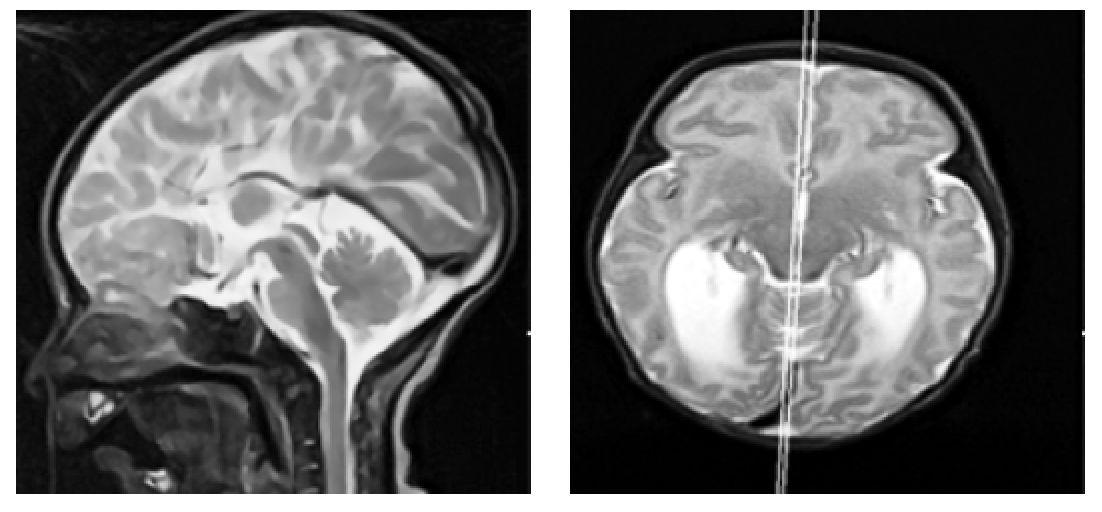

1. Аксиальная проекция - по орбитомеатальной линии (рис.1).

2. Сагиттальная проекция - вдоль третьего желудочка через водопровод мозга (рис. 2).

3. Коронарная проекция - по слуховым нервам (рис. 3).

Рис. 1. Пример позиционирования срезов по орбитомеатальной линии в сагиттальной плоскости для получения изображения в аксиальной проекции при проведении магнитно-резонансной томографии головного мозга на примере Т2 ВИ пациенту восьми месяцев жизни.

Рис. 2. Пример позиционирования срезов вдоль третьего желудочка через водопровод мозга в аксиальной плоскости для получения изображения в сагиттальной проекции при проведении магнитнорезонансной томографии головного мозга на примере Т2 ВИ пациенту восьми месяцев жизни

Рис. 3. Пример позиционирования срезов по слуховым нервам аксиальной плоскости для получения изображения в коронарной проекции при проведении магнитно-резонансной томографии головного мозга на примере Т2 ВИ пациенту восьми месяцев жизни